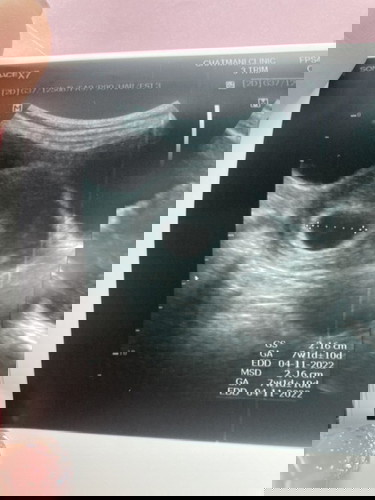

อัลตราซาวด์ตอน 5 วีค กับ 3 วัน เห็นแต่ถุงตั้งครรถ์ แม่ๆทั้งหลาย เห็นตัวอ่อนตอนกี่วีคคะ #ขอบคุณสำหรับคำตอบค่ะ